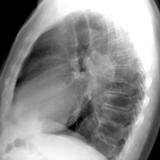

RLL Collapse  1 Lateral

Date: 02/28/2004

Views: 3309